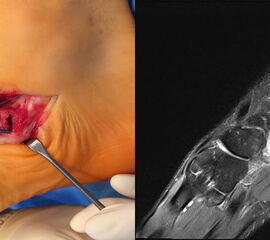

- Bei unklarem Befund kann die Bildgebung mittels MRTvervollständigt werden. Das MRT zeigt eine mögliche Aktivierung der Synchondrose bzw. erlaubt auch andere Differentialdiagnosen (Tendonose der Tibialis posterior Sehne, Verletzung Deltaband, Verletzung Pfannenband) auszuschließen (Abb. 3) 6 (Szeimies 2014).

Bei lange anhaltenden postoperativen Beschwerden ist die Rückfußstellung erneut zu überprüfen 22. Ein Rückfußvalgus führt zur einer Mehrbelastung des Ansatzes der Tibialis posterior Sehne, so dass ggf. die Indikation einer Kalkaneusosteotomie zur Korrektur der Rückfußachse zu überprüfen ist. Weitere mögliche Ursachen anhaltender Beschwerden kann eine unvollständige Abtragung der Knochenkanten sein, Beschwerden im Bereich der Narbe sowie eine Irritation der Tibialis posterior-Sehne. Als weiterführender Diagnostik empfiehlt sich in dieser Situation die MRT-Untersuchung, gegebenenfalls in Verbindung mit einer Computertomografie, da kleine Verkalkungen und Knochenkanten im MRT häufig übersehen werden.